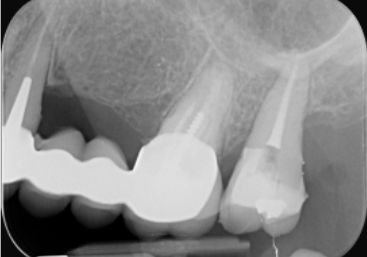

Endodontiste

Endodontie